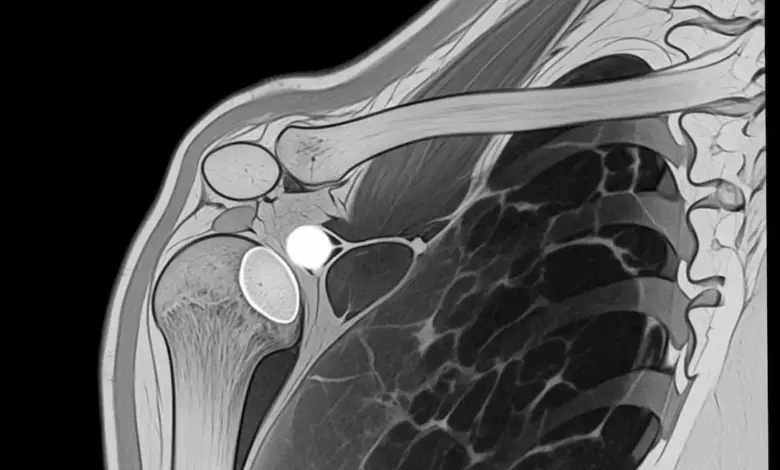

- A ressonância magnética do ombro é o exame mais útil para visualizar cistos paralabrais e alterações do labrum.

O termo “cisto no ombro” engloba cisto sinovial, cisto paralabral e cisto periarticular. Em comum, eles representam acúmulo de líquido sinovial fora do local onde ele deveria ficar.

Alguns cistos aparecem na região posterior do ombro e podem se associar a rupturas póstero-superiores do labrum.